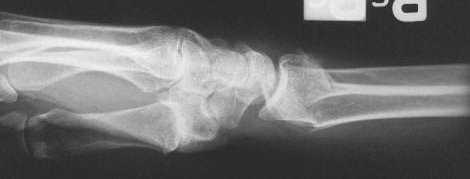

Clinical Example: Distraction plate fixation distal radius fracture

distal radius fracture